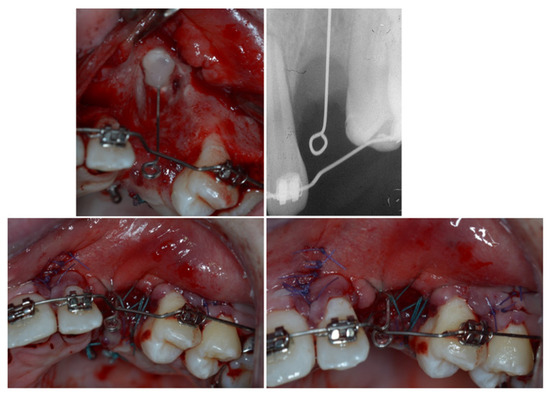

2.2. Radiographic Findings

3. Therapeutic Interventions